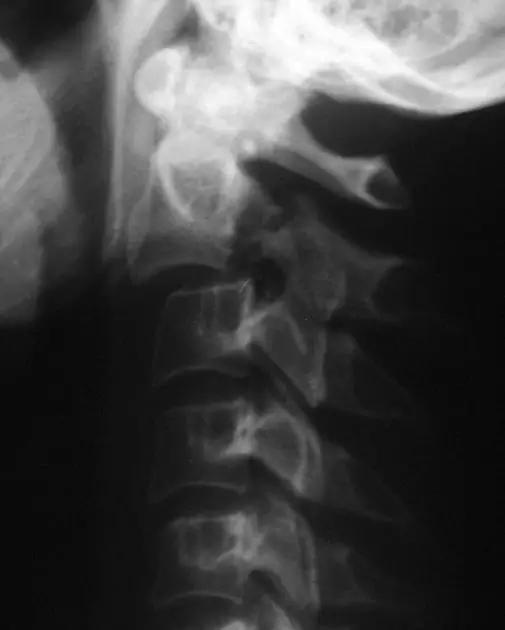

2. Teardrop 骨折

特指颈椎椎体前下方带有骨折块者,包括屈曲型和伸展型。伸展型损伤指椎体前下缘或下一椎体前上角形成三角形骨块,提示椎体前方稳定结果破坏,治疗不宜伸展位。屈曲型指压缩致使椎体前方三角骨块被挤出如泪滴状,提示前后方稳定结构均遭破坏,常伴脊髓损伤。常需手术治疗。

伸展型 Teardrop 骨折(来源:Radiopaedia)